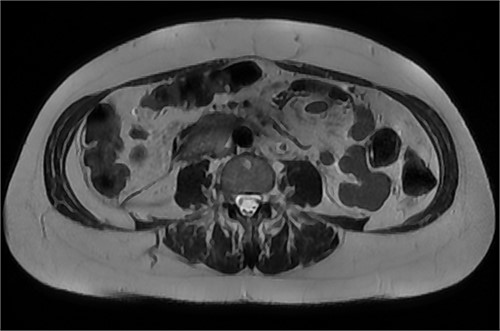

Continued observation, analgesia and fasting. On Day 2 post-admission, the patient had an urgent upper gastrointestinal endoscopy, which showed no abnormality. No ulcer, compression or inflammation was found. After the gastroscopy, the patient was started on a normal diet, which she tolerated well, and her pain had also improved. A progress CT was performed on Day 5, which showed a mild increase of the periduodenal collection with mass effect on the duodenum and evidence of mild biliary tree dilatation with the common bile duct measuring 11 mm. There was no sign of gastric outlet obstruction (Figs 7 and 8).

CT abdomen, coronal view. Slight interval decrease in size of previously identified periduodenal hematoma.

CT abdomen, axial view. Slight interval decrease in size of previously identified periduodenal hematoma.